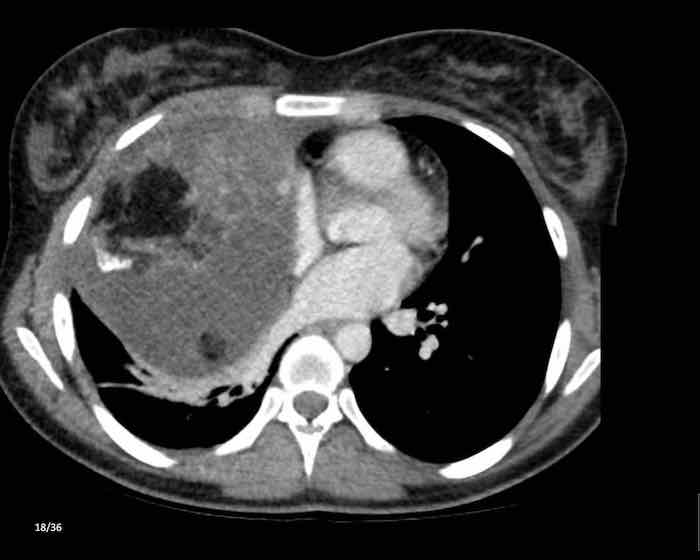

Các hình ảnh này của một phụ nữ 65 tuổi có tiền sử mắc bệnh Graves, một rối loạn tự miễn liên quan đến tình trạng cường chức năng tuyến giáp.

CT được thực hiện vì lý do ho ra máu.

Hình ảnh

Có một tuyến ức to lớn, cồng kềnh chứa mô mỡ đại thể.

Đây là hình ảnh điển hình của tăng sản tuyến ức.

Tăng sản tuyến ức trong bệnh Graves có liên quan đến tình trạng dư thừa hormone tuyến giáp và kháng thể kháng thụ thể thyrotropin.

Tình trạng này thường cải thiện sau khi điều trị thành công bệnh Graves.